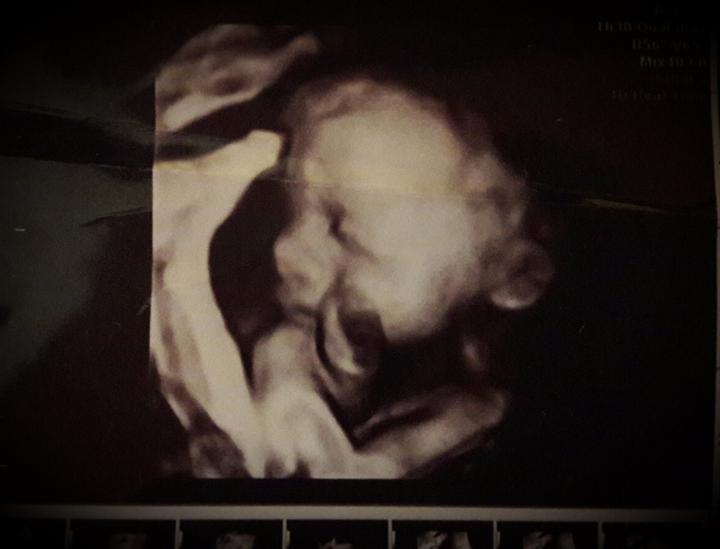

babule kde sne na SR boli na 3D alebo 4D sono?? (V rámci TN, NR...alebo kde konkret v BA?) kolko ste platili a kolko dopredu ste sa museli objednat?? dakujem